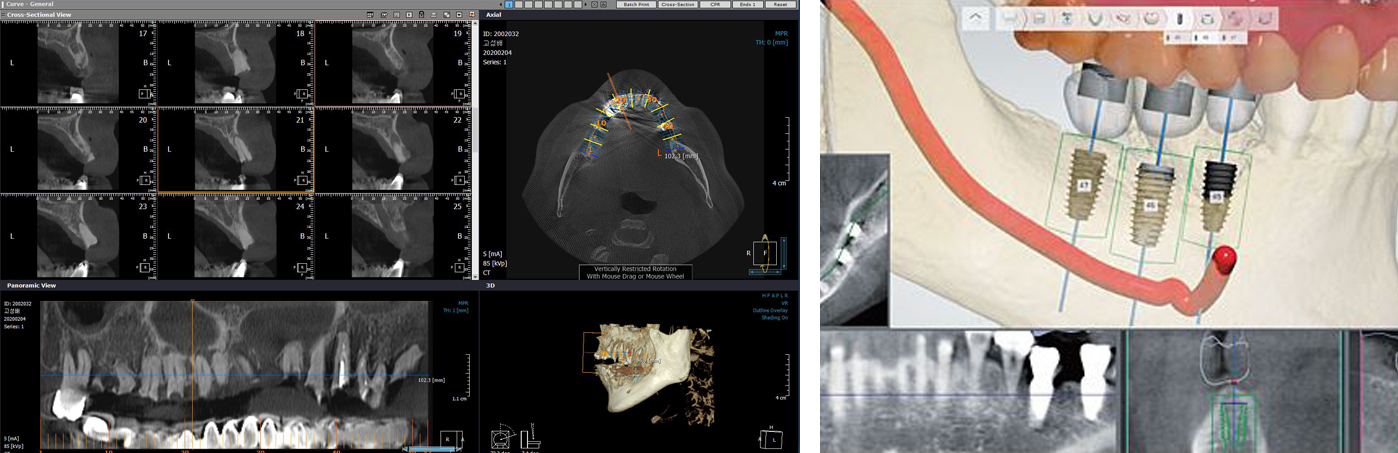

스마트 진단시스템

스탠다드 치과는 안면전체를 입체적으로 촬영할 수 있는 3D CT 임플란트의 고정력을 측정하는 기계 등

고난이도 전체임플란트만을 위한 수술키트 등 전문수술장비를 갖추고 있습니다. 정확한 진단자료를 바탕으로

각 분과별 전문의가 대학병원 시스템과 동일하게 함께 협진하여 수술계획을 세워 수술을 집도합니다.